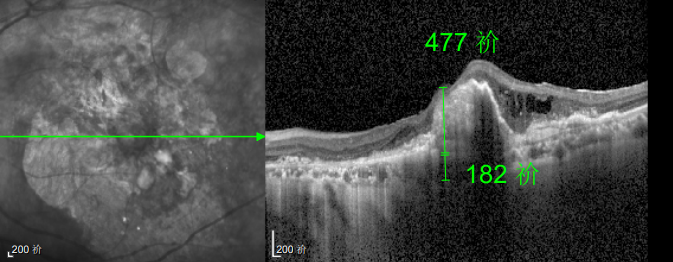

△規(guī)劃化治療后的左眼